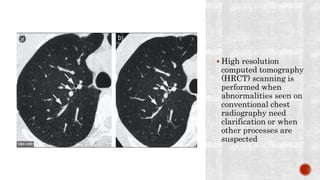

 High resolution

computed tomography

(HRCT) scanning is

performed when

abnormalities seen on

conventional chest

radiography need

clarification or when

other processes are

suspected